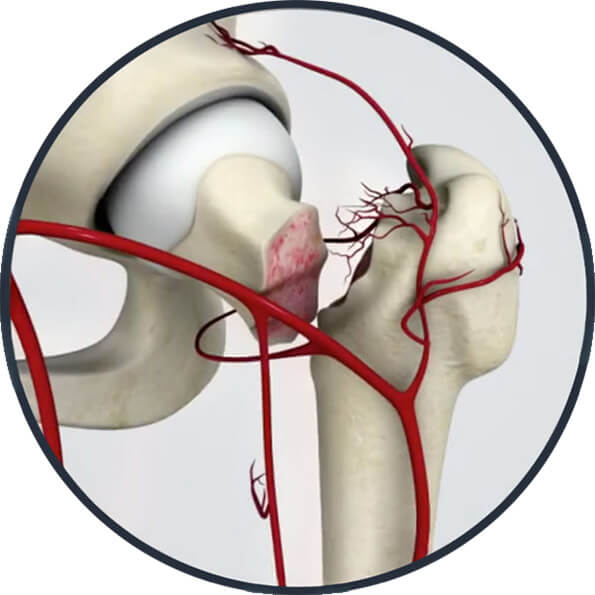

3 Fratura Descolada do Colo Femoral 4 Fratura do Colo Femoral / Vascularização

Fig. 4 - Fratura do Colo Femoral / Vascularização